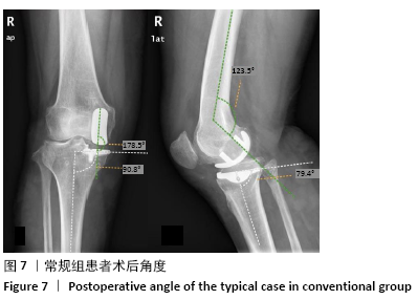

Yu Yinghao, Zhao Jijun, Liu Dongcheng, Chen Yuhao, Feng Dehong. Clinical significance of preoperative planning assisted unicompartmental knee arthroplasty with digital imaging system for fixed-bearing prosthesis[J]. Chinese Journal of Tissue Engineering Research, 2021, 25(21): 3324-3331.